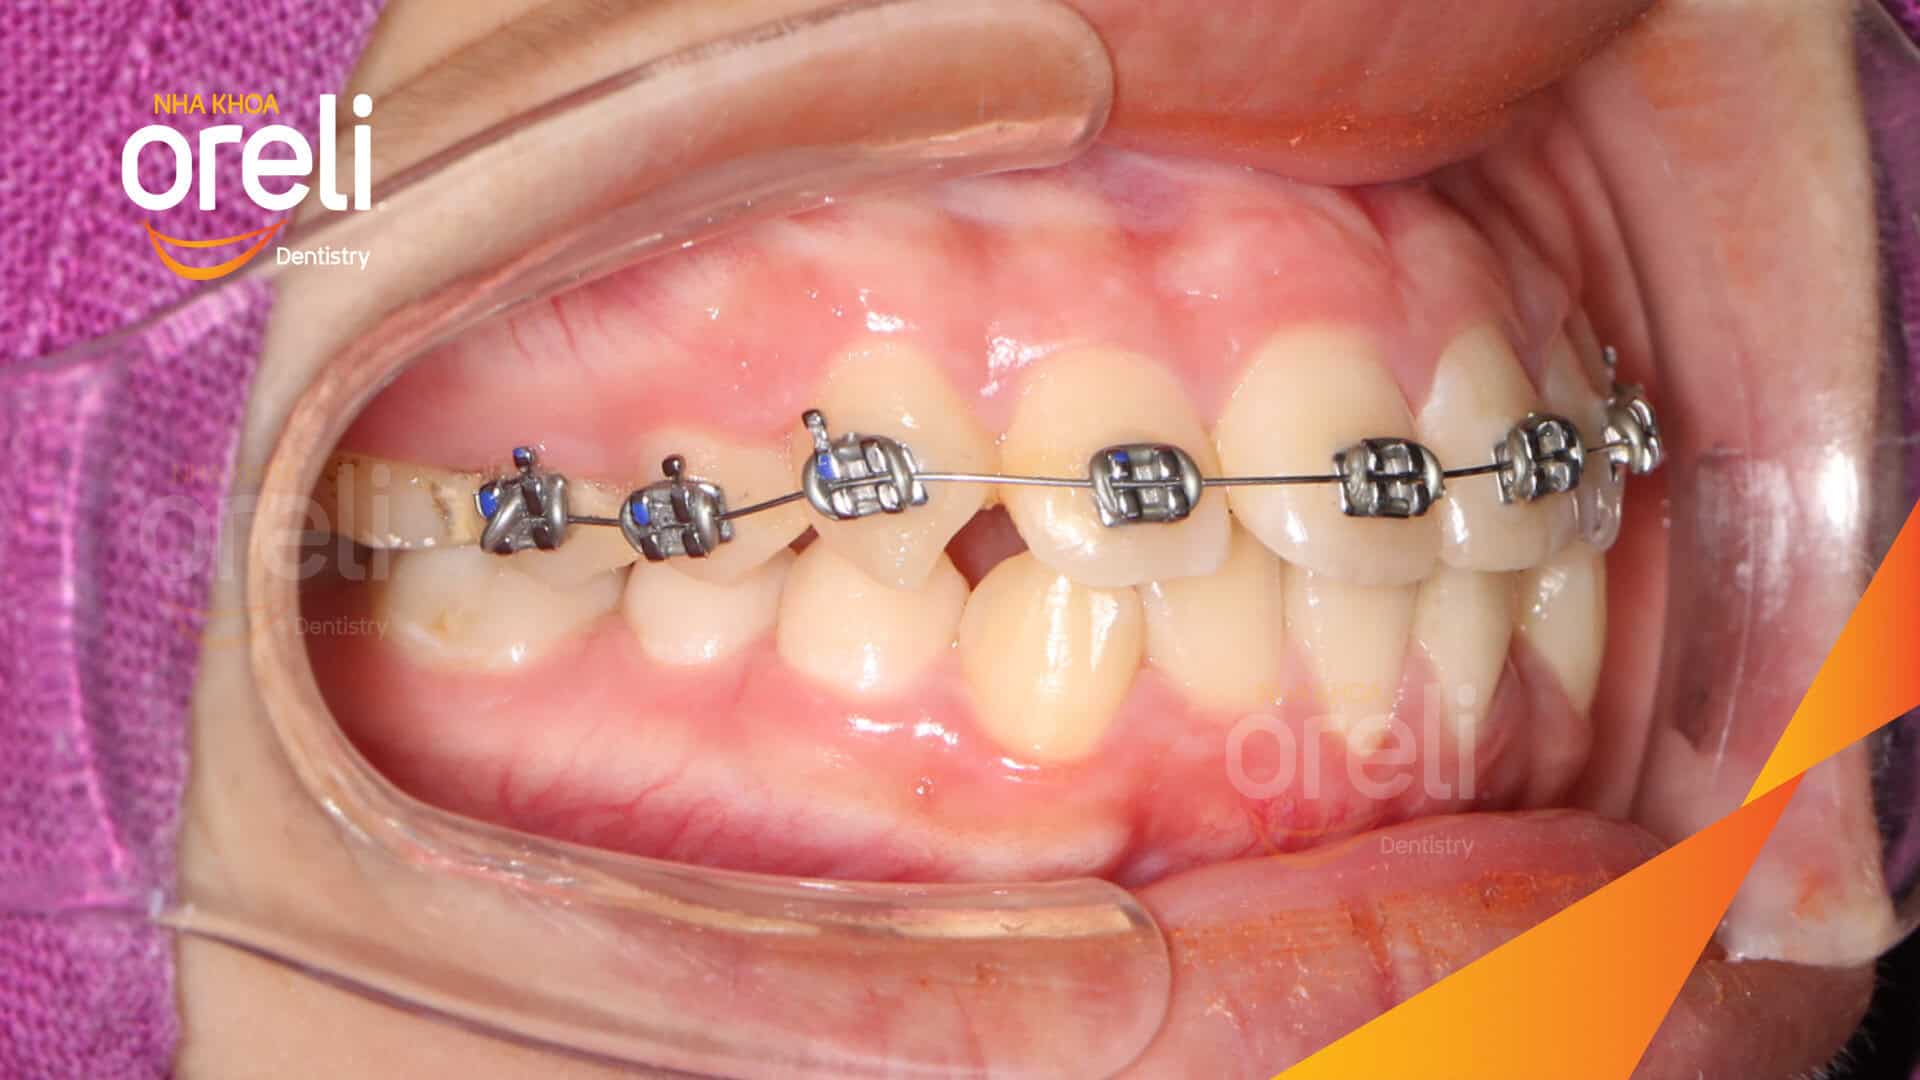

Tình trạng: Nhô xương ổ, trục răng nghiêng trước hai hàm, độ nhô môi nhiều

Giải pháp: Nhổ răng 4 chỉnh hô

Thời gian: 24 tháng

Kết quả: Nụ cười hài hòa, mặt nghiêng đẹp, trục răng cửa đứng